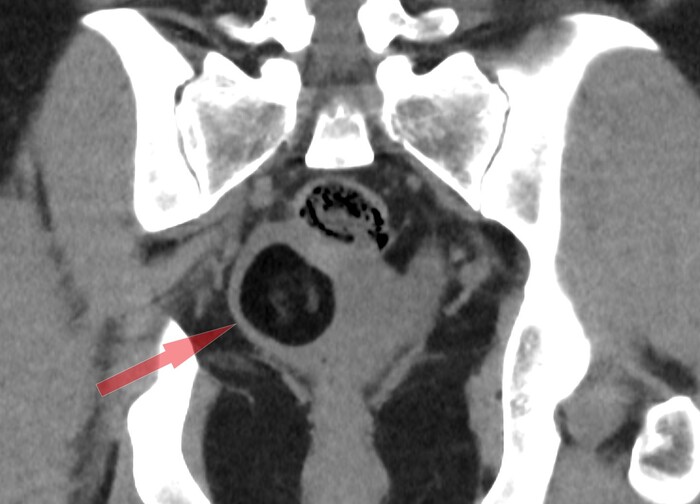

Дополнительно обращал на себя внимание геморрагический (с примесями крови) выпот в дугласовом пространстве:

Со средней плотностью 29 HU (вода 0 HU- +10 HU, жир -200 HU - 0 HU, вода с примесями крови - выше +20 HU):

Проблема была больше в выпоте с кровью в малом тазу, т.к. это не нормально (у женщин детородного возраста допускается некоторое количество свободной жидкости в малом тазу, но в совсем небольших и без значительных примесей крови), а значит тут, скорее всего, имеется острая патология, и скорее всего правого яичника в виде перекрута оного вокруг своей оси на фоне тератомы. При повторной оценке корональных срез было локализовано место перекрута (симптом "водоворота" сверху от правого яичника):